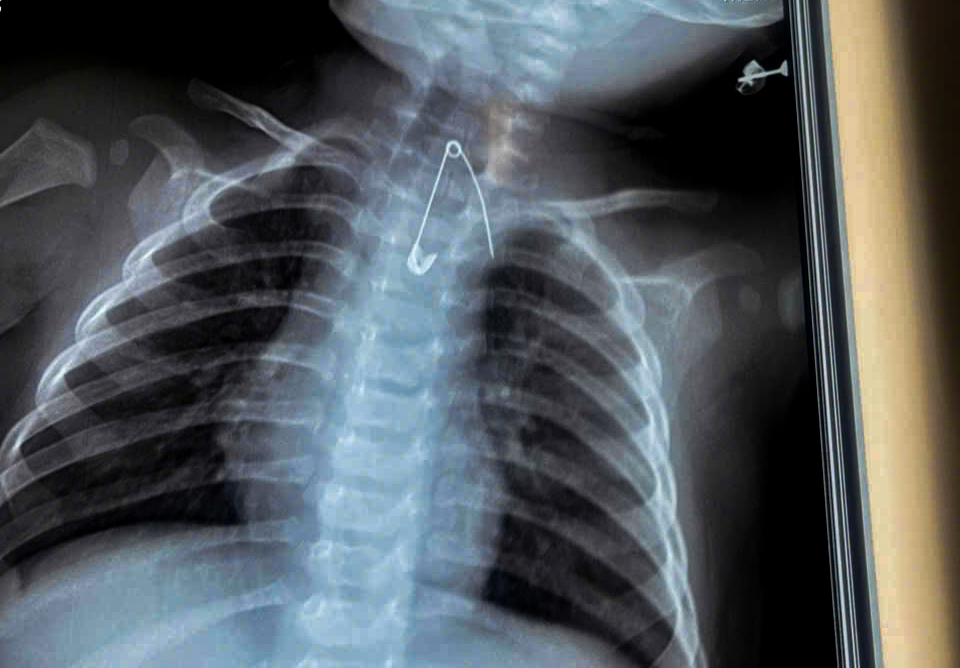

Kim băng bé Đ. (7 tháng tuổi) nuốt và trôi đến vị trí nguy hiểm đến tính mạng - Ảnh: Bệnh viện cung cấp

Trường hợp thứ hai là bé trai Đ. (7 tháng tuổi), ngụ xã An Trạch, tỉnh Cà Mau, được gia đình đưa đến bệnh viện trong tình trạng sốt, ho, khò khè kéo dài 2 ngày. Khai thác bệnh sử cho thấy trong khoảng 3 tháng gần đây, bé thường xuyên bị ho, viêm hô hấp tái đi tái lại.

Người nhà cho biết gia đình có thói quen dùng kim băng ghim bùa bình an vào áo của bé. Qua thăm khám lâm sàng và thực hiện các xét nghiệm cận lâm sàng, các bác sĩ phát hiện một dị vật là kim băng nằm trong mô mềm, ở vị trí rất nguy hiểm, sát động mạch chủ.

Dị vật này tiềm ẩn nguy cơ gây tổn thương mạch máu lớn, xuất huyết ồ ạt và đe dọa tính mạng nếu không được xử trí kịp thời.

Bệnh nhi sau đó được ê kíp phẫu thuật viên của bệnh viện can thiệp, lấy dị vật ra an toàn, ngăn ngừa các biến chứng nghiêm trọng có thể xảy ra.